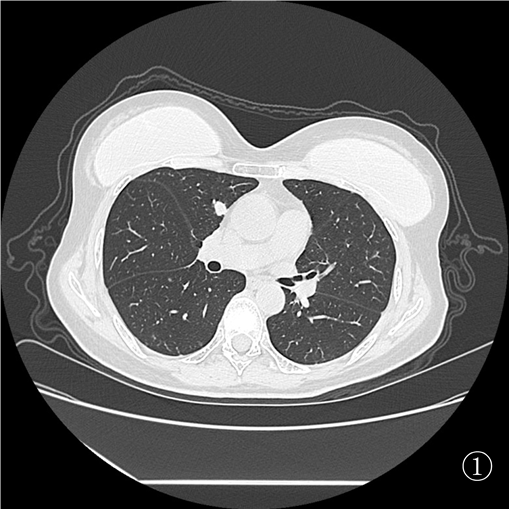

为进一步明确诊断,制定后续治疗方案,杨志祥主任组织讨论后拟行 CT 引导下肺占位穿刺活检,由于右肺占位(图①)毗邻升主动脉及肺动脉,初步拟定行图②左肺占位穿刺活检。

患者俯卧定位扫描(图③):由于胸腔及肺组织受压,左肺占位距离膈肌<1 cm,行穿刺活检必然损伤膈肌,可能造成严重并发症。于是决定经胸前穿刺右肺占位活检(图④),但由于病灶小于 1 cm 且邻近大血管,必须精准制导(图⑤)。穿刺后扫描局部少许出血,未见气胸(⑥)。